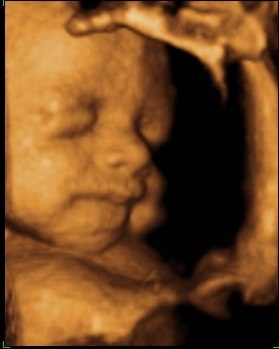

så var vi til 3D scanning i fredags. Så vild en oplevelse.. Hun er bare helt perfekt.

hun vejede 1423g, og så var hun en uge foran så det var da super dejligt at vide at lille pigen har det super og lever luxus derinde i maven

vi var heldige med at hun var rigtig aktiv plus vi også så hende med åbne øjne